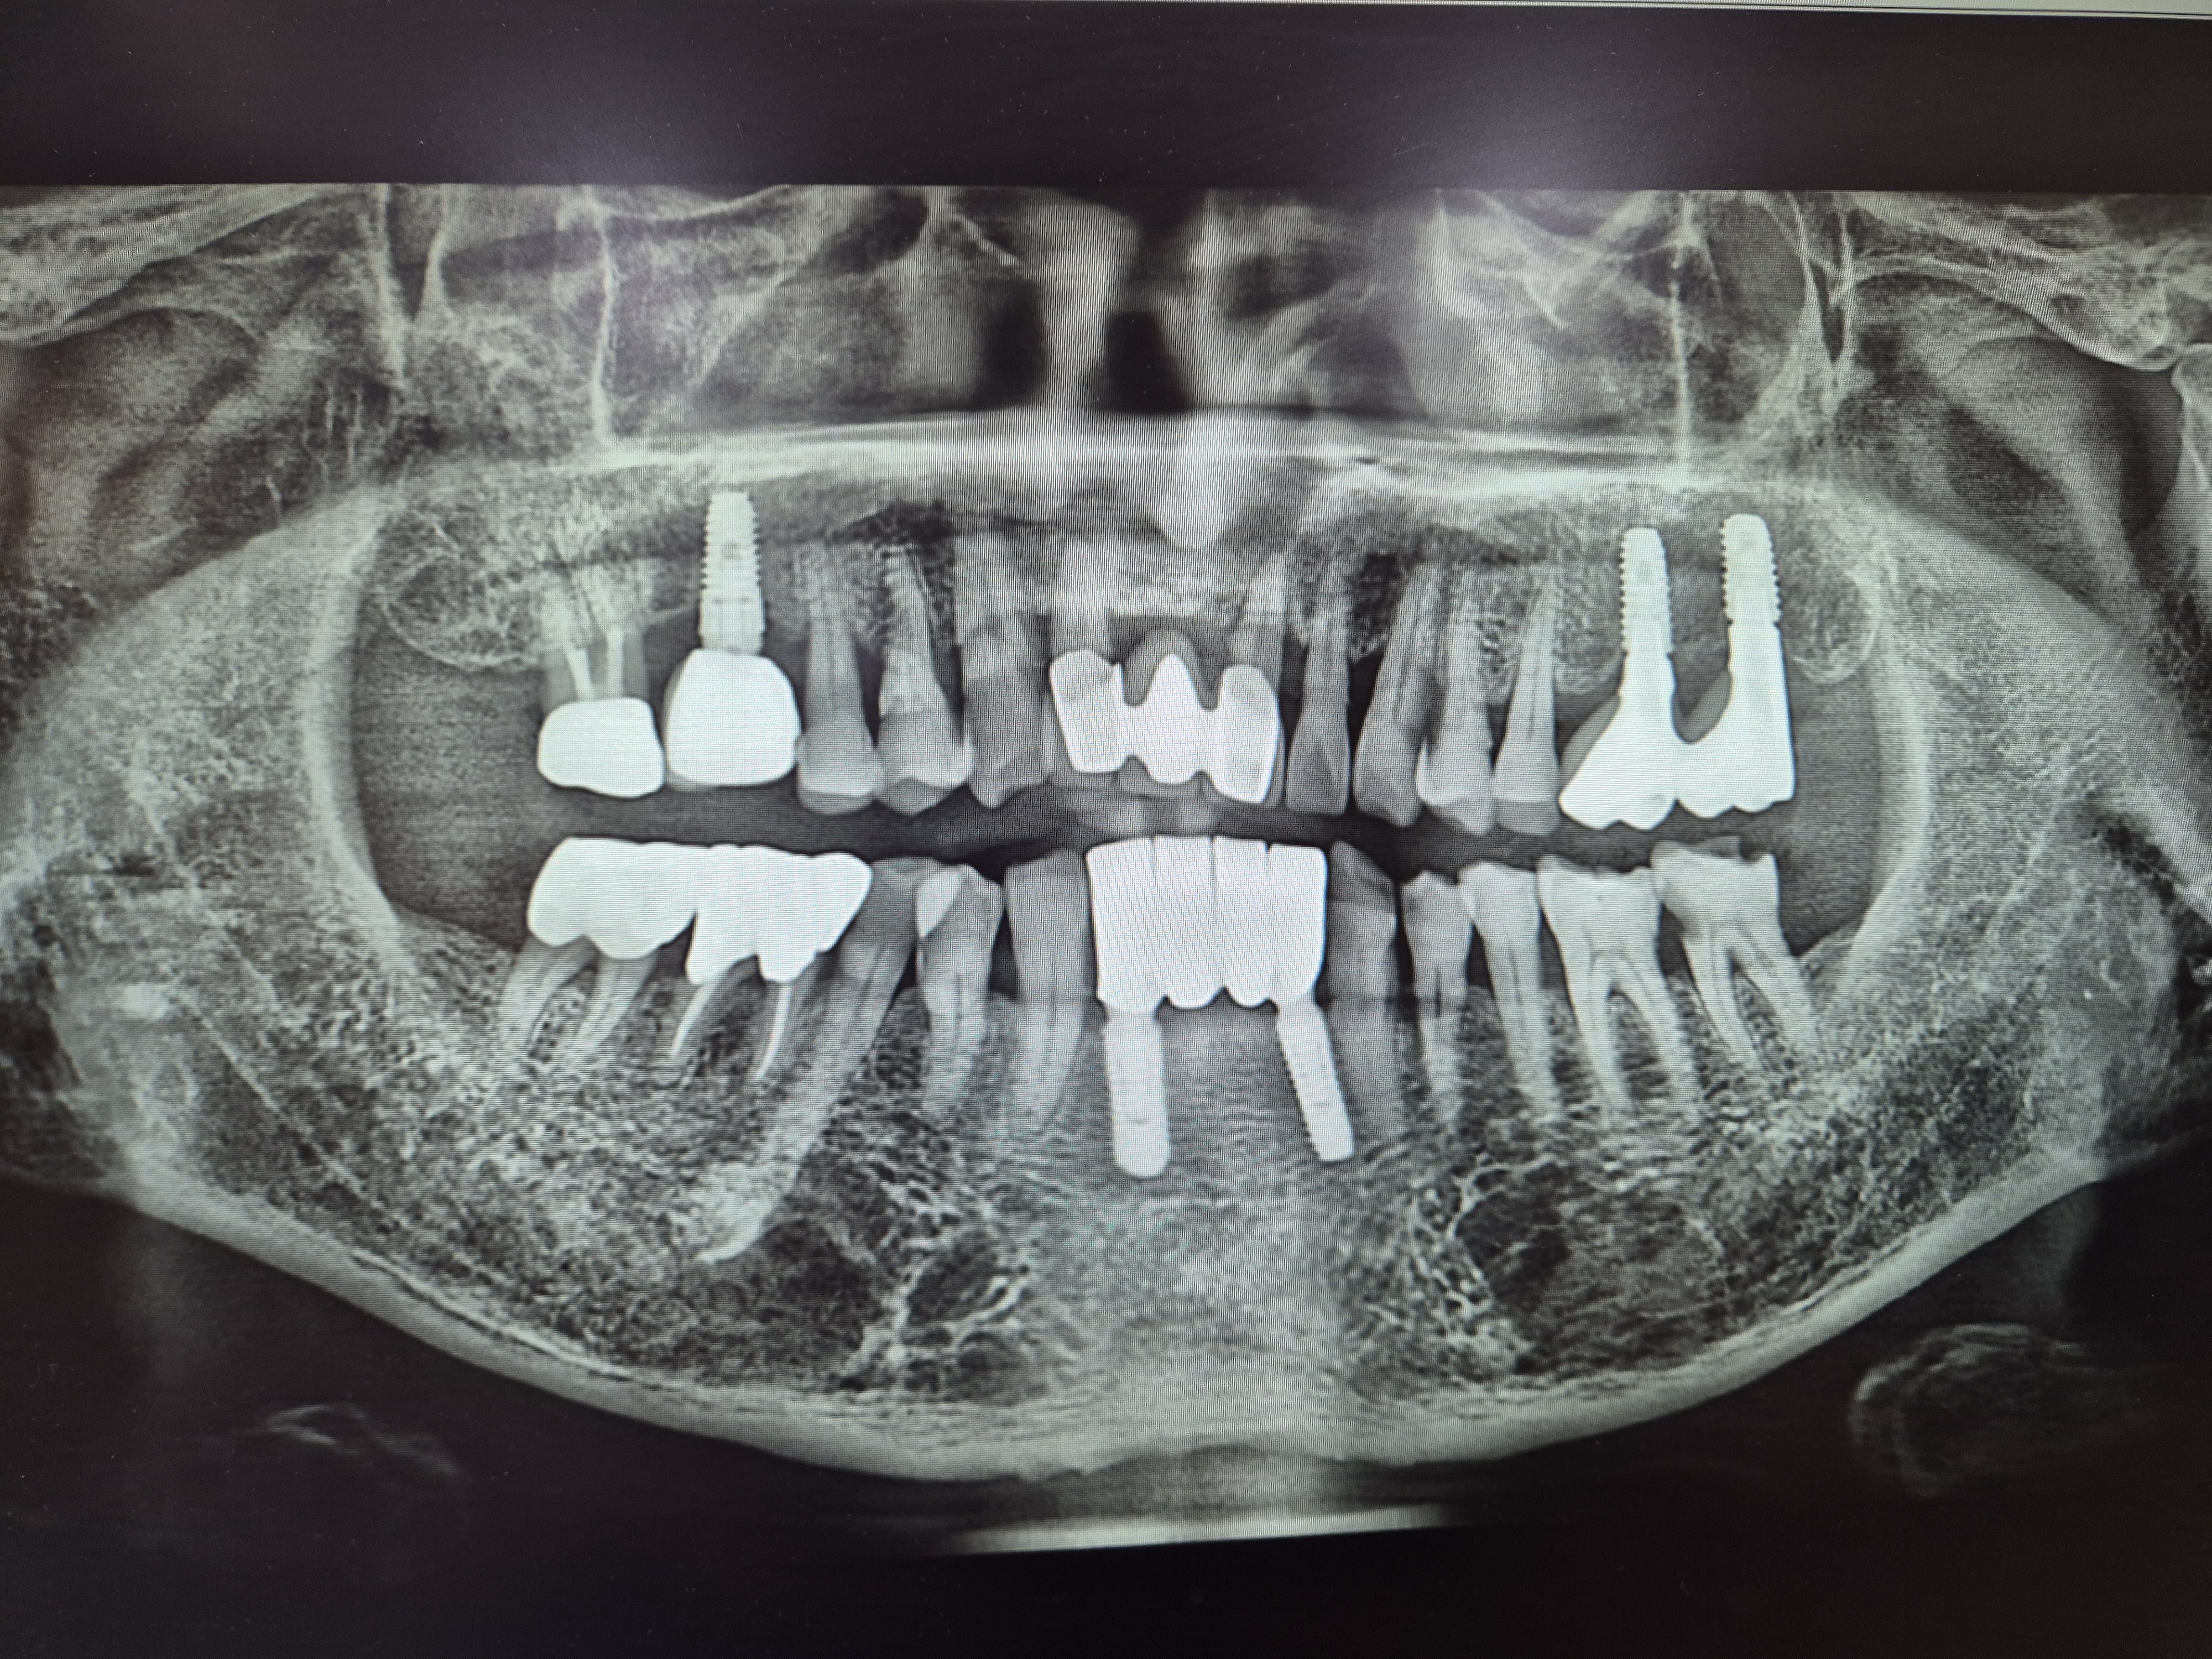

치아사진을 보니 5개의 임플란트와 덧씌우거나 치료받은 이빨이 10개정도.

총체적으로 건강하지못한 치아상태이다.